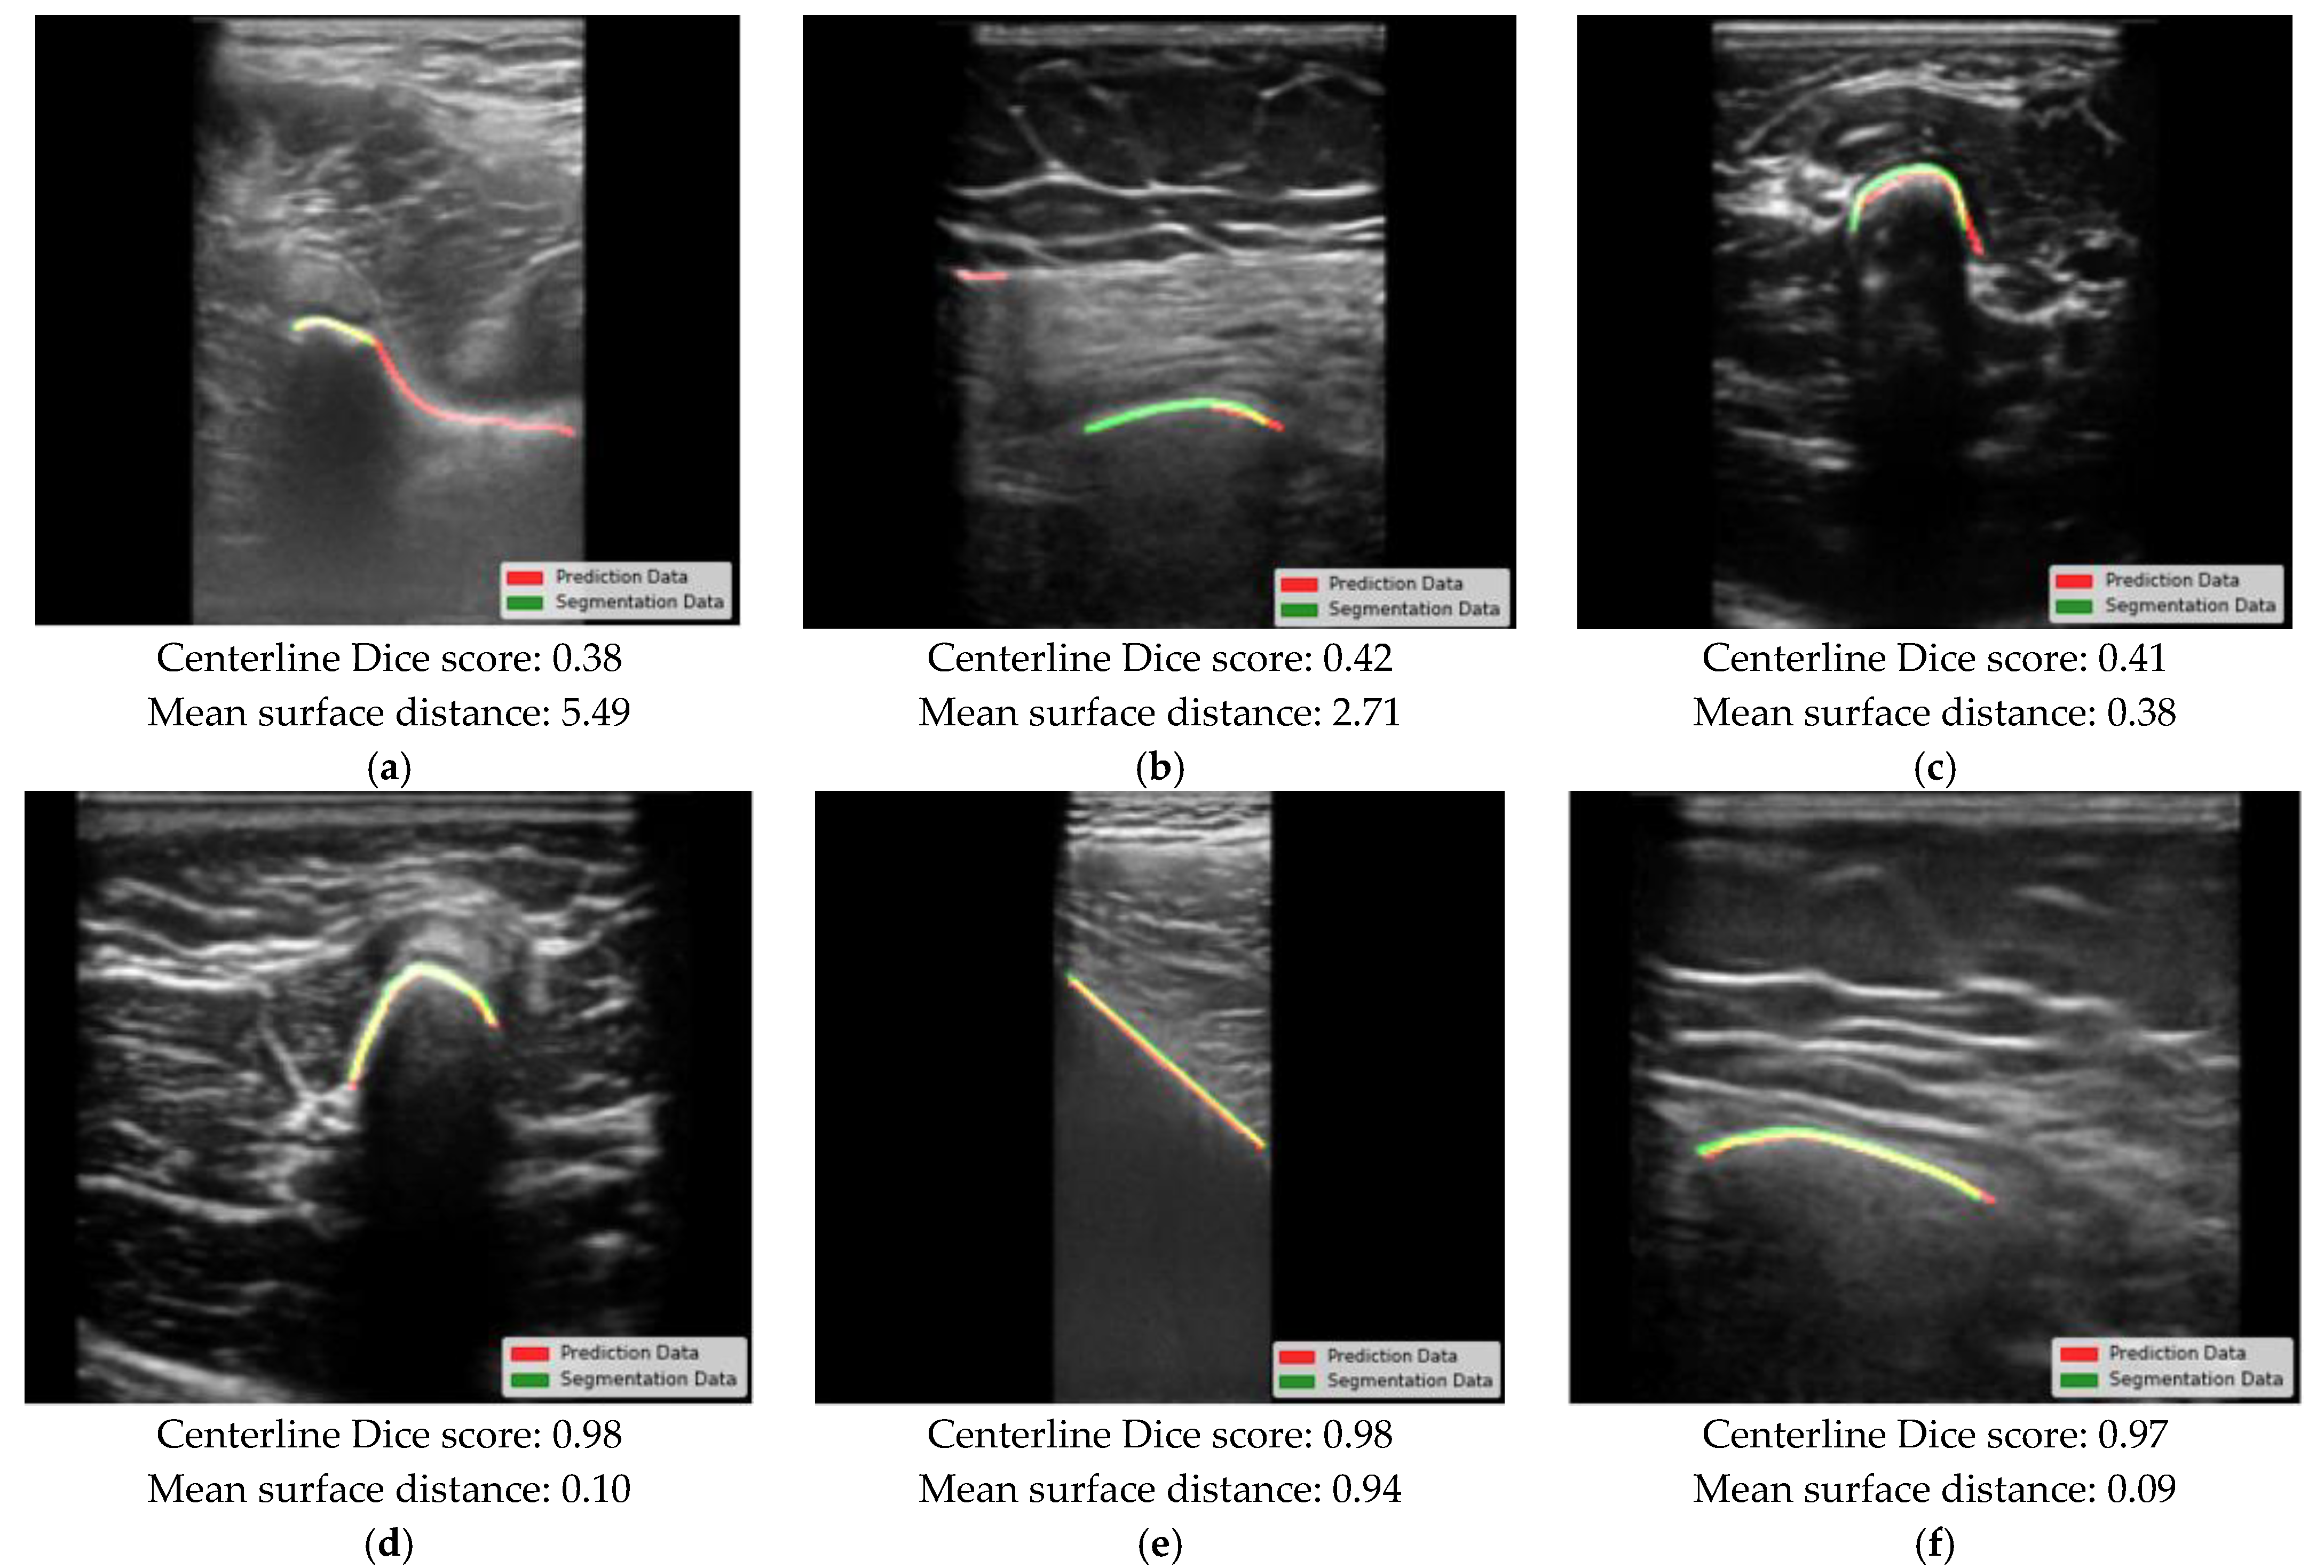

3. Results